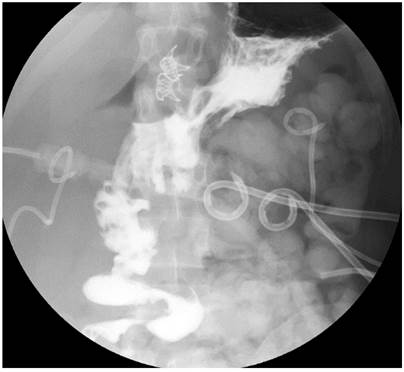

A gastrointestinal tract X-ray was performed as a follow-up during the postoperative stage, showing no pyloric continuity with adequate patency of the gastrojejunostomy. In addition, a contrasted abdominal CT scan showed a decrease in the intra-abdominal collection without extravasation of the contrast medium.

On the fifth day after the endoscopic procedure, an imaging follow-up of the digestive tract confirmed no pyloric continuity with adequate patency of the gastrojejunostomy. A contrasted abdominal tomography showed a decrease in the intra-abdominal collection without contrast medium extravasation (Figures 4 and 5).